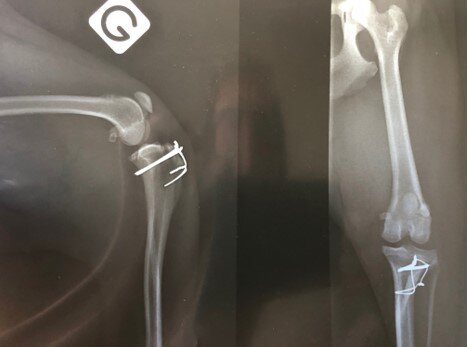

Boston Terrier femelle, 5 ans, 7,3 kg

Douleurs chroniques post-opératoires (suite reprise luxation rotule : sulcoplastie trochléaire et transposition de la crête tibiale) : Douleurs spontanées, de type décharges électriques, décalées du temps opératoire (6 mois), réfractaires aux AINS. Prise en charge avec succès des douleurs neuropathiques par un traitement de fond (gabapentine 50 mg BID) et par la gestion des accès paroxystiques (tramadol 30 mg BID)